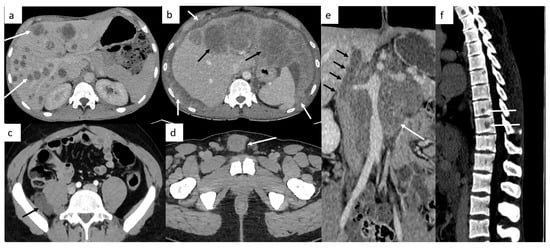

Other sites include liver, bones and rarely, testicular metastasis may occur to adrenals, kidneys, spleen, pleura, pericardium, peritoneum or retroperitoneum in very advanced disease (Figure 2). In case of large retroperitoneal lymph nodes, an extension may occur into the inferior vena cava in the form of tumor thrombus (Figure 2).

Figure 2.

Other sites of metastatic disease. In advanced stages, abdominal CT can show different sites of metastases including liver ((a,b), black arrows), peritoneal carcinomatosis ((b), white arrows), retroperitoneal carcinomatosis (c), cutaneous metastases in front of pubis (d). In case of large retroperitoneal lymph nodes ((e), white arrows), a tumor thrombus in the inferior vena cava can be found ((e), black arrows). Spinal bone CT shows several vertebral metastases (f).

Brain imaging is not routinely performed but is indicated in symptomatic patients, in patients with high risk factors such as choriocarcinoma type tumor (likely hemorrhagic metastases), serum marker HCG > 10,000, or in advanced metastatic disease, including supradiaphragmatic nodal disease (Figure 3).